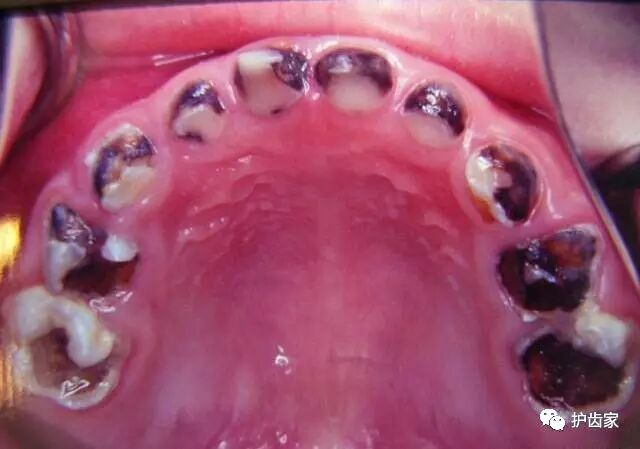

8.是否有糖尿病?!

许多时候,糖的不平衡会显示出牙龈健康的快速变化,包括肿胀,出血和敏感性增加。结合起来,唾液也可能会改变,可能会增加牙齿腐烂,这些都可能是糖水平失去控制的迹象,所以牙科医生可能会提醒病人检查糖尿病。